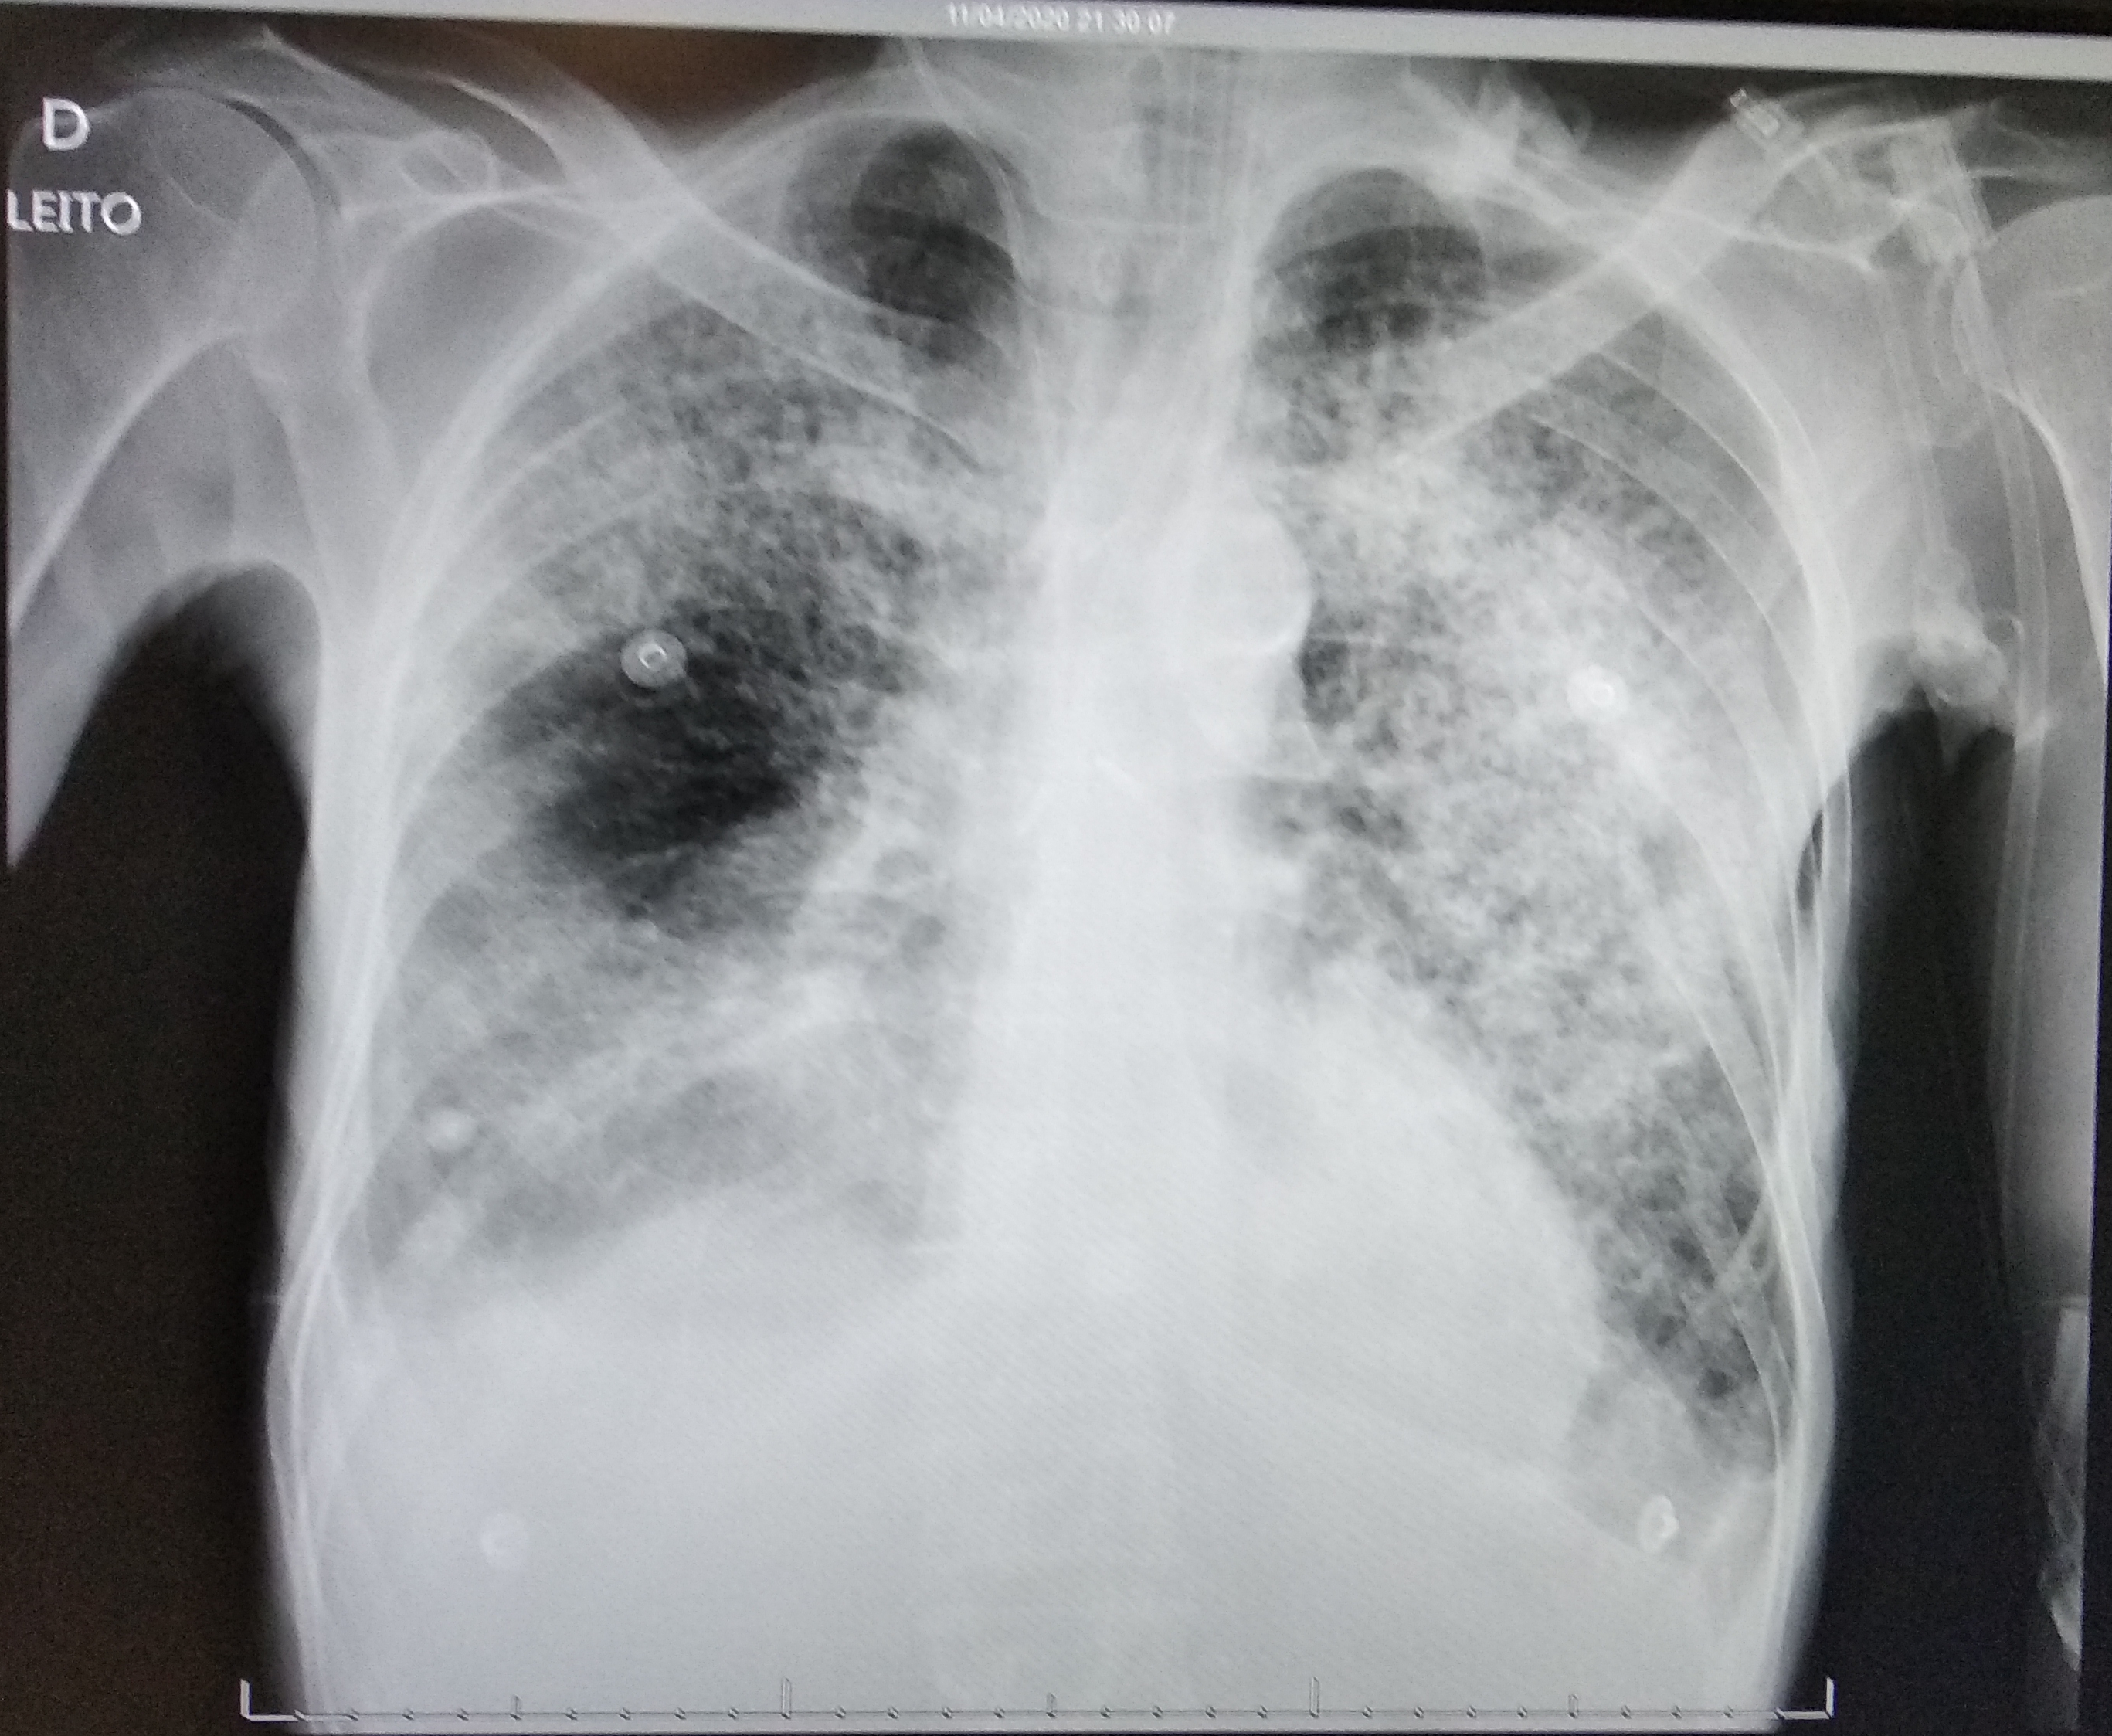

Demanda: Estudo de Caso Clínico (qual o meio de obte-lo: contrato NDA, orçamento?) das análises que fizemos (em anexo) de raio x e tomografia computadorizada obtidos em base pública realizado sob plataforma pública de deep learning com modelo abastecido por datasets públicos de pacientes suspeitos de contágio com covid-19 e outras doenças respiratórias****.

3 - Treinar o Modelo Mellieri Human de Rede Neural Convolucional para detectar o COVID-19 e outras doenças respiratórias em imagens de raios-X e tomografia computadorizada.

4 - Notamos que um paciente pode ter um misto de complicações respiratórias (Covid e Pneumonia por exemplo).

Qual impacto disto nas pesquisas e soluções para combate ao covid-19 como vacinas em função do estágio da doença a exemplo do metadados anexos já que os diagnósticos podem ser únicos para cada paciente no tempo?